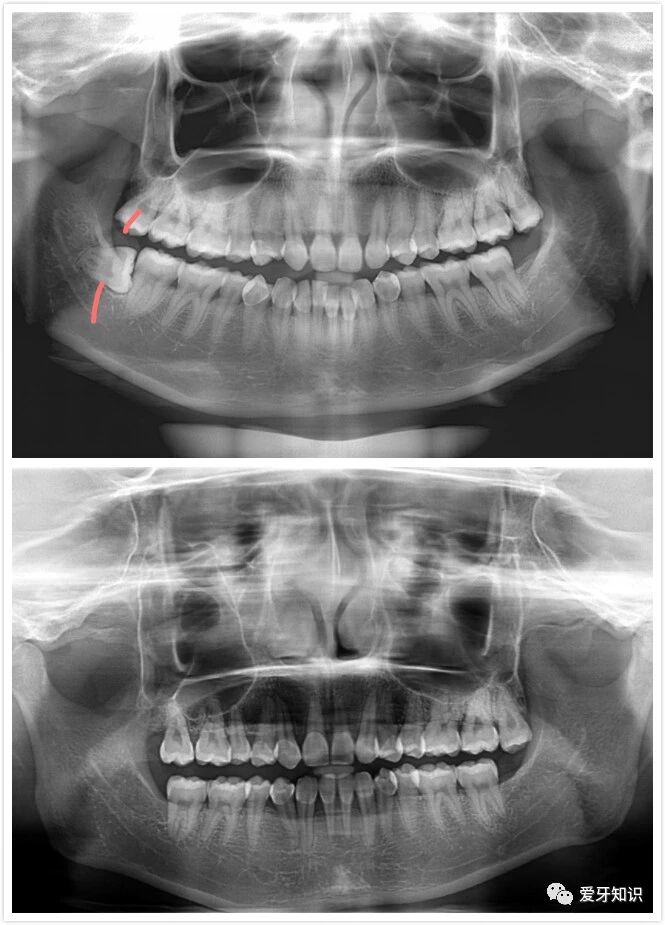

拍片

拍X光牙齿及头部颌骨照片。目的是确定颌面及牙列畸形的分类类型,骨骼发展方向等。以利于以后制定准确的矫正方法。

拔牙

按照医生制定的方案,分批次的拔除需要拔出的正畸牙,一般的人大概需要拔4个左右牙齿,部分特殊的,比如智齿多的,牙齿过于密集的也有拔8个左右。(有的人则不需要拔,仅磨牙就可以了)如果有蛀牙什么的就会先补好,有牙结石的也会先洗牙。(拔牙的目的是为了空出空间,来给那些因牙齿拥挤导致不整齐的牙齿规位,至于拔牙的缝隙到时候会合拢,不用过分的担心)